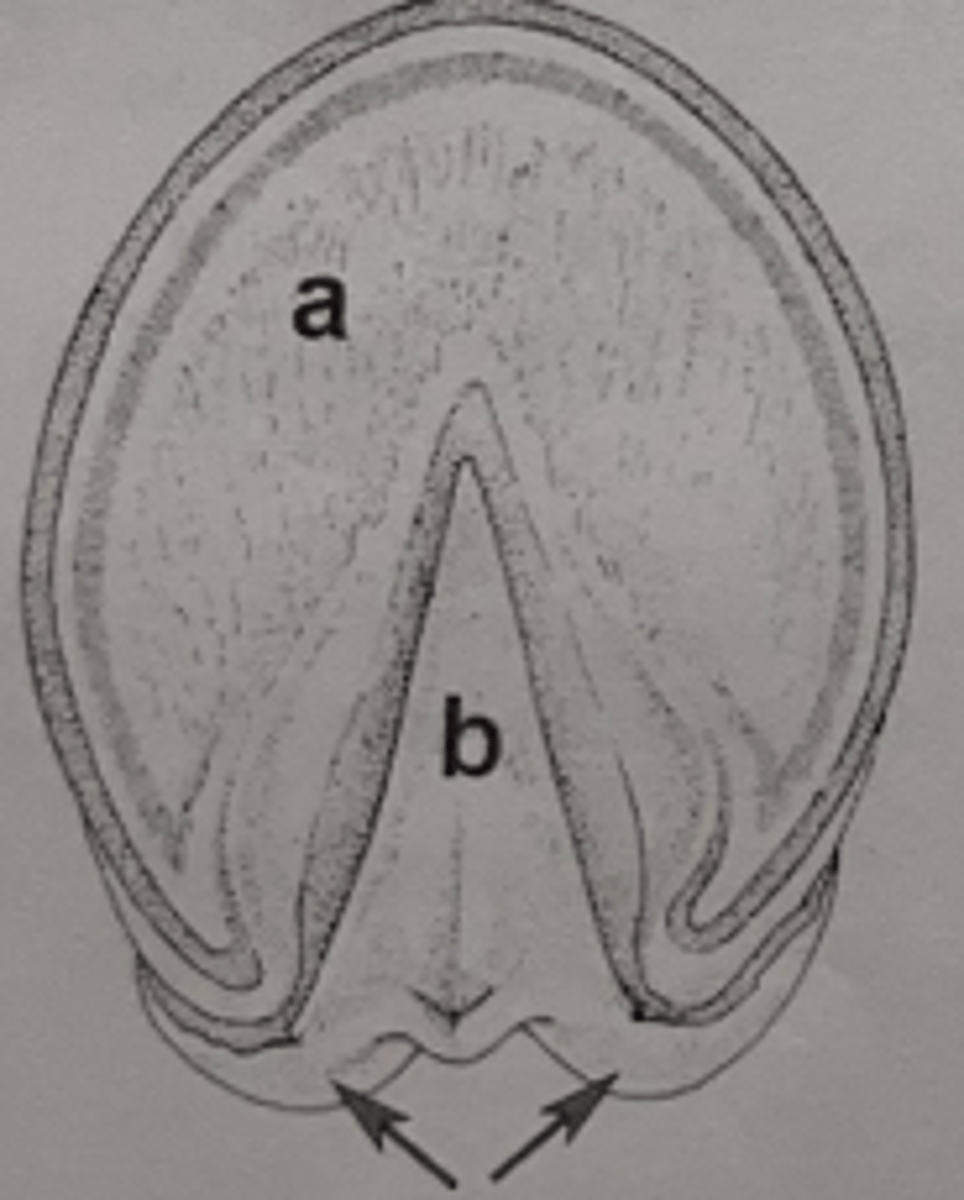

sole

What region of the hoof is A?

deep digital flexor tendon

Which tendon would be encountered by a penetrating foreign body entering the hoof at B?

PIII (Coffin bone)

Which bone does deep digital flexor tendon insert on?

bulb of heel

Which structure is indicated by arrows?